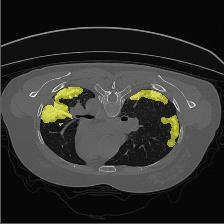

Medical image segmentation is one of the most fundamental tasks concerning medical information analysis. Various solutions have been proposed so far, including many deep learning-based techniques, such as U-Net, FC-DenseNet, etc. However, high-precision medical image segmentation remains a highly challenging task due to the existence of inherent magnification and distortion in medical images as well as the presence of lesions with similar density to normal tissues. In this paper, we propose TFCNs (Transformers for Fully Convolutional denseNets) to tackle the problem by introducing ResLinear-Transformer (RL-Transformer) and Convolutional Linear Attention Block (CLAB) to FC-DenseNet. TFCNs is not only able to utilize more latent information from the CT images for feature extraction, but also can capture and disseminate semantic features and filter non-semantic features more effectively through the CLAB module. Our experimental results show that TFCNs can achieve state-of-the-art performance with dice scores of 83.72\% on the Synapse dataset. In addition, we evaluate the robustness of TFCNs for lesion area effects on the COVID-19 public datasets. The Python code will be made publicly available on https://github.com/HUANGLIZI/TFCNs.